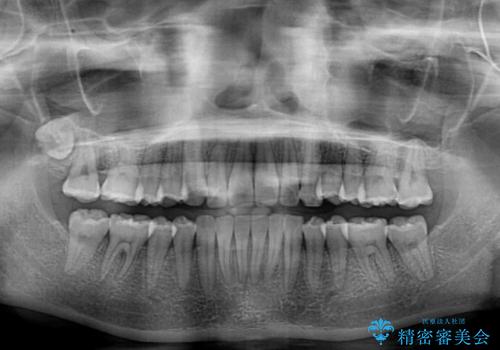

奥歯の咬み合わせはしっかりと改善され、前歯の突出感も改善されました。